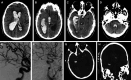

Background and objectives: Hemorrhagic subcortical vascular lesions such as cavernous malformations (CM) and arteriovenous malformations (AVM) can be neurologically devastating. Conventional open surgical resection is often associated with additional morbidity. The BrainPath® (NICO Corp.) transsulcal tubular retractor system offers a less-invasive corridor to deep-seated lesions. Our objective was to describe a single-center experience with the resection of subcortical hemorrhagic vascular lesions in adult and pediatric patients using the BrainPath® system.

Methods: The departmental database was queried for patients who underwent resection of a hemorrhagic CM, AVM, or cerebral aneurysm through the BrainPath® tubular retractor system between January 2017 and September 2021. All patients underwent either postoperative MRI (for patients with CM) or digital subtraction angiography (for patients with AVM or aneurysm). Demographic and clinical characteristics, preoperative and postoperative imaging features, operative details, and surgical and clinical outcomes were extracted through a retrospective review of the medical records.

Results: Fourteen patients (mean [SD] age 32.3 [23.9] years; 7 (50%) female) underwent BrainPath®-based resection of a deeply seated CM (n = 7), AVM (n = 6), or ruptured cerebral aneurysm (n = 1). The mean maximal lesion diameter was 21.5 (12.6) mm. The mean operative time was 134 (53) minutes. Residual lesion was present in 2 patients, both of which underwent repeat BrainPath®-assisted surgery for complete resection. All lesions were completely resected or obliterated on postoperative MRI or digital subtraction angiography. At a mean follow-up of 4.1 (1.1) years, the median modified Rankin Scale score was 1 (range 0-6).

Conclusion: In a well-selected cohort, we show the effective use of BrainPath® tubular retractors for resection or obliteration of subcortical hemorrhagic vascular lesions. This report further exemplifies the expanded role of the endoport system beyond that of intracerebral hemorrhage and tumor. Further study will elucidate the impact of this less-invasive brain retraction technique on clinical outcome in patients with vascular lesions.